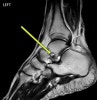

T2 MRI : 족근동 증후군(Sinus tarsi syndrome)